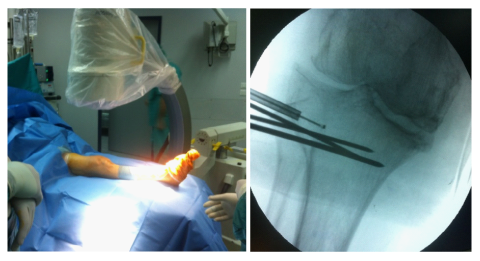

The optimal position for balloon placement was predetermined using the CT scanning. In the operating room the patient was placed in supine position on the operating table and a fluoroscopic unit was readily available. Under spinal anesthesia, a clinical stability test was applied, which did not reveal any ligamentous injury. After skin preparation and draping, a trocar was introduced in the lateral tibial plateau through a stub incision and advanced to the predetermined position - below the depressed fragment - using fluoroscopic control. Three Kirschner wires were placed just below the trocar, to act as a palisade, supporting the subsequent balloon inflation (Figure 2). We started slowly inflating the balloon with contrast solution to an initial pressure of 50 psi, without any radiographic evidence of balloon asymmetry, indicative of malpositioning. We then fully inflated the balloon to approximately 250psi, effectively raising the depressed tibial plateau (Figure 3).

Figure 2 Operative room and draping, trocar and supporting K-wires introduction.